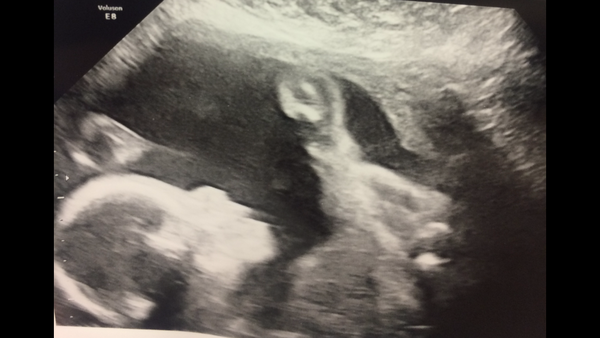

Bubs almost 25w. Finally moved and on her back and legs over her shoulders. With Right hand holding right leg

Lovely pic Blondes

Nice to have a decent pic for once - usually get a head shot if lucky as usually on stomach looking at my back

Ooh! Great picture!